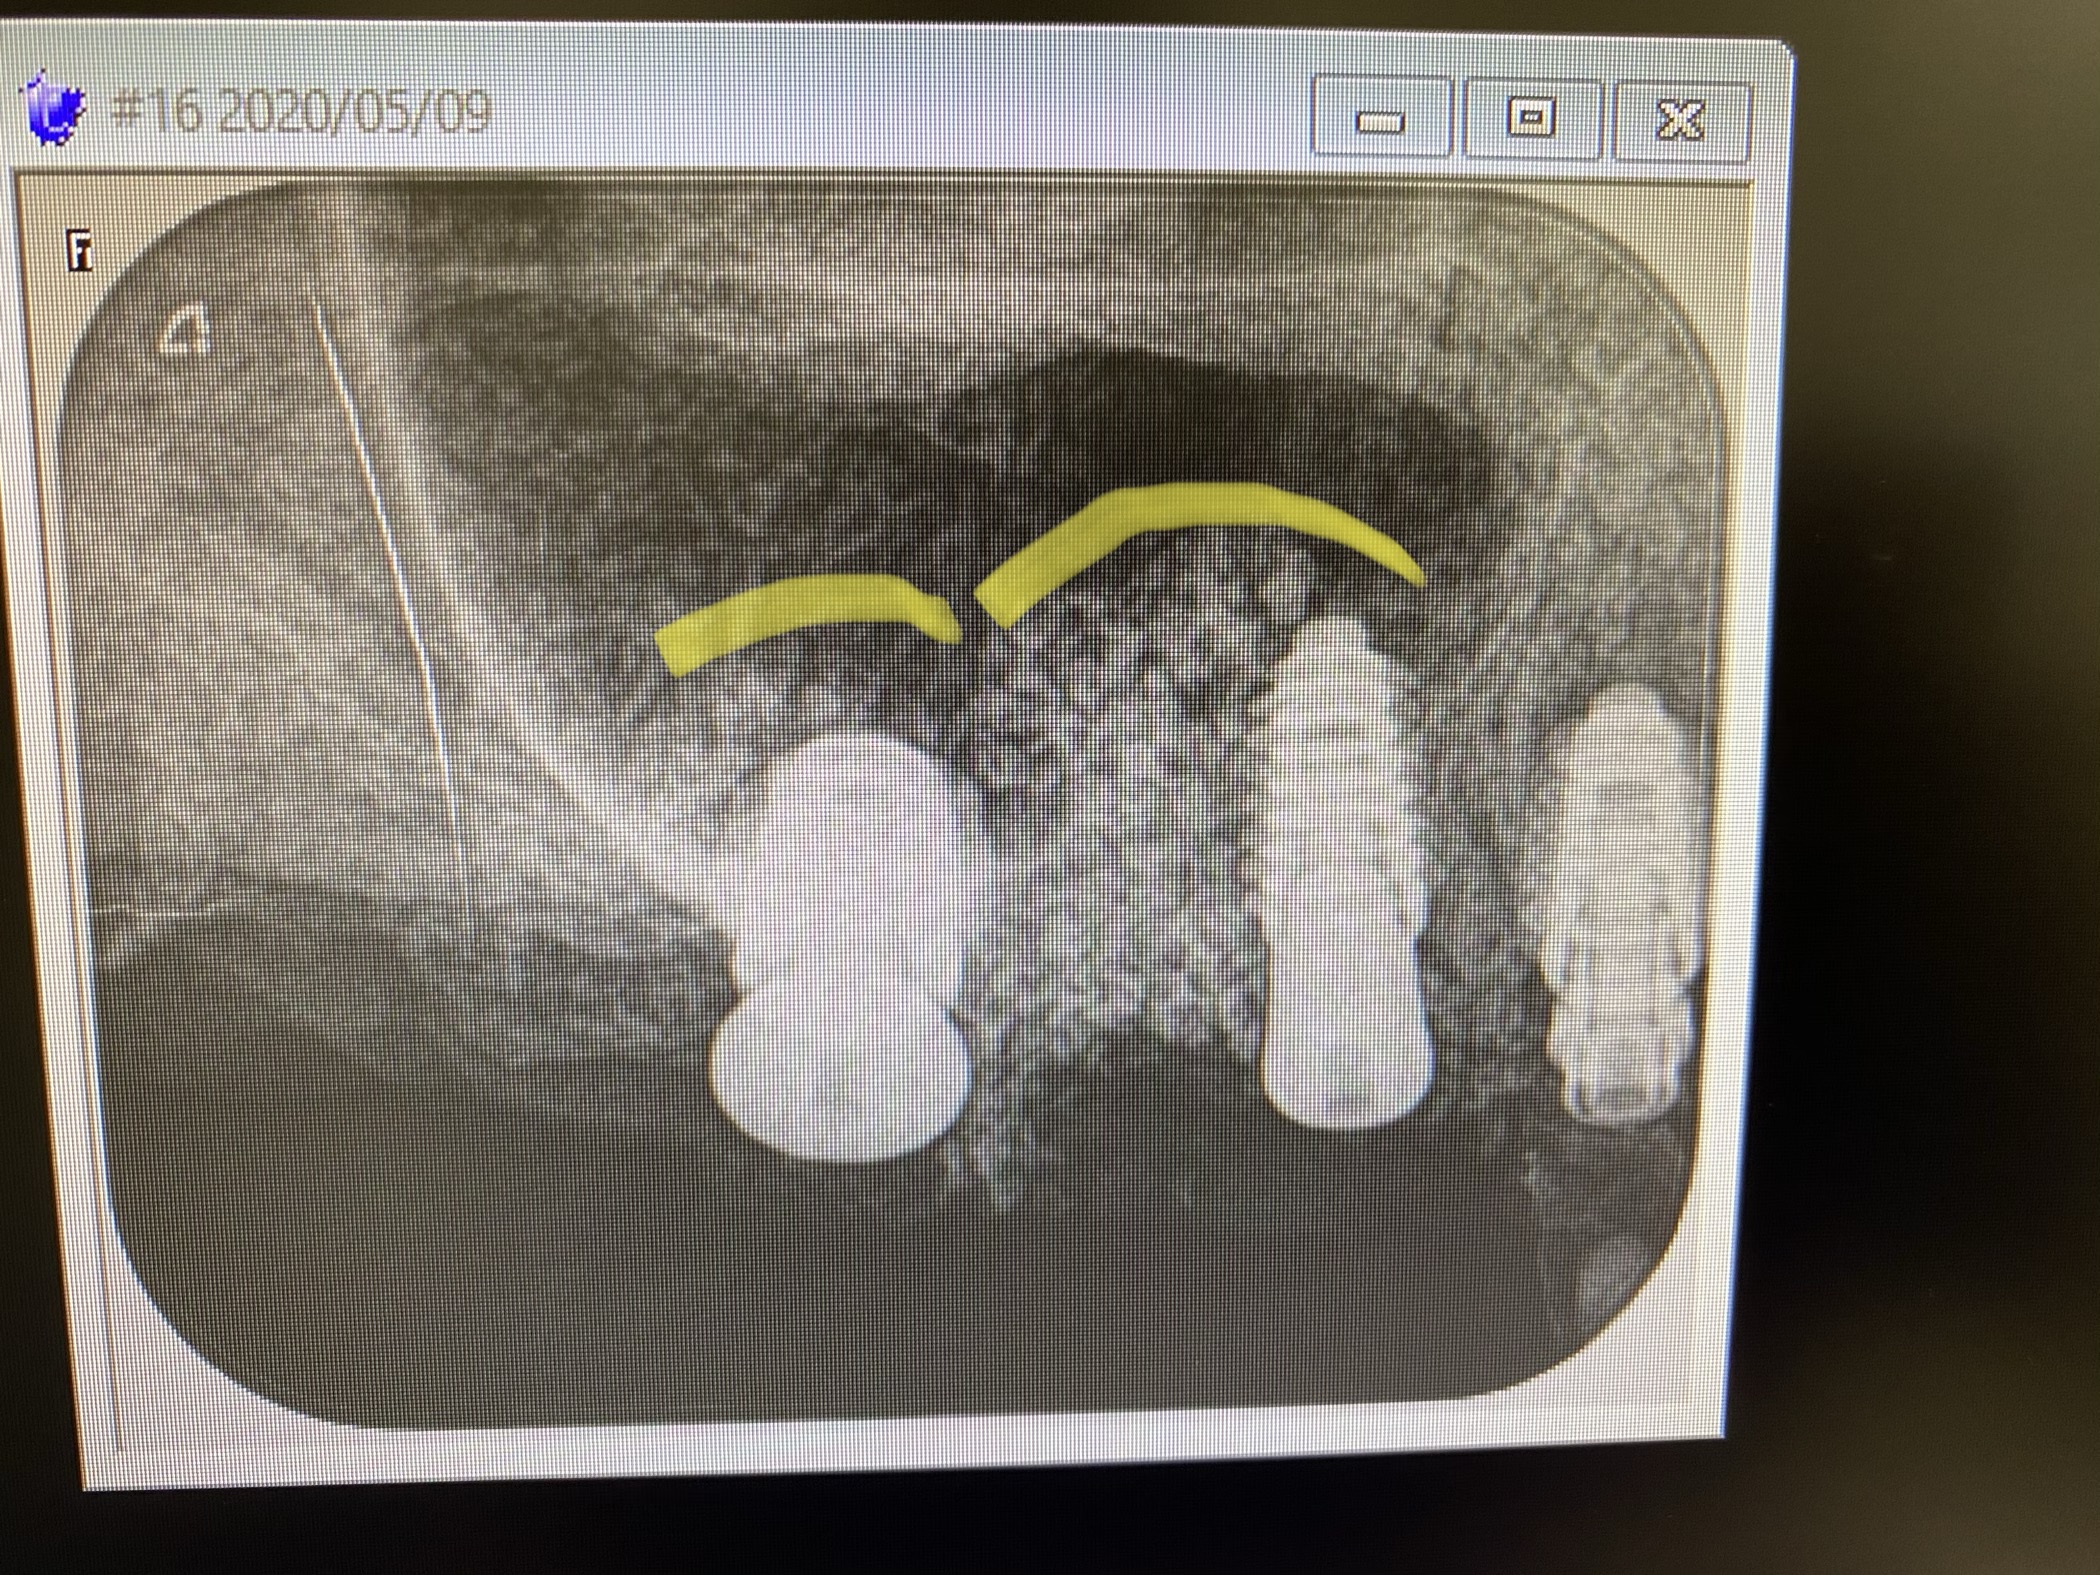

ソケットリフト法を併用した2本同時埋入する非常に難易度の高いオペが須田寛昌執刀医により行われました。

(右上5.6番のインプラントオペ)

綺麗なドーム状にシュナイダー膜を持ち上げ造骨組織が収まっています。